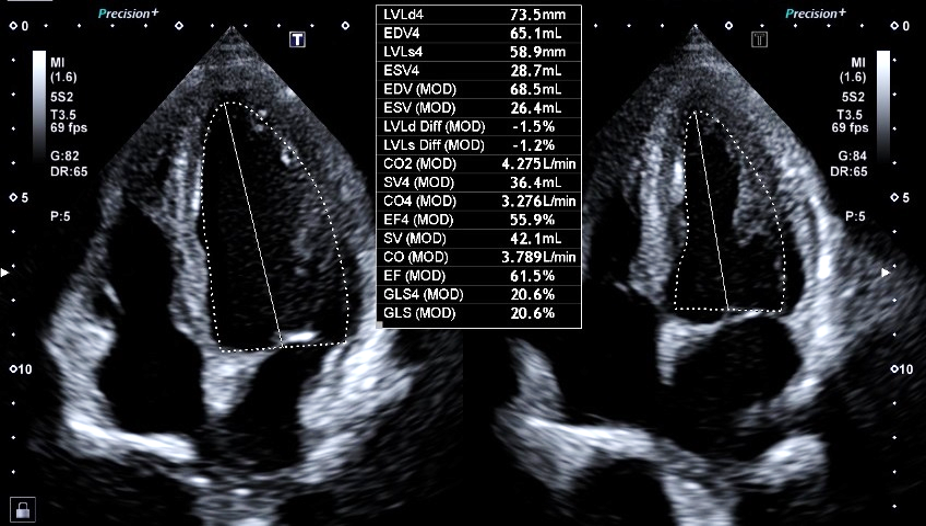

心臓超音波検査

心臓超音波検査は、心臓のリアルタイムの動きを観察することが出来ます。超音波検査の優れた点は、このリアルタイム、専門的に言い換えれば時間分解能が高い点と非常に安全かつ簡便に施行できる点になります。心エコー検査は、心臓の大きさや動き、壁の厚さ(心肥大の診断に用います)を計測することが可能です。

その中で心臓の動き(壁運動評価)は、心エコー検査の中でも、熟練が必要だと言われてます。また読影する人によりばらつきが生じることもあります。

AI技術を用いて自動でEF(左室駆出率)を算出する機能と同時に、詳細な壁運動の指標をカラーマップで提示でき、収縮のタイミングもグラフで確認可能となり詳細な解析が可能となります。

2D Wall Motion Tracking